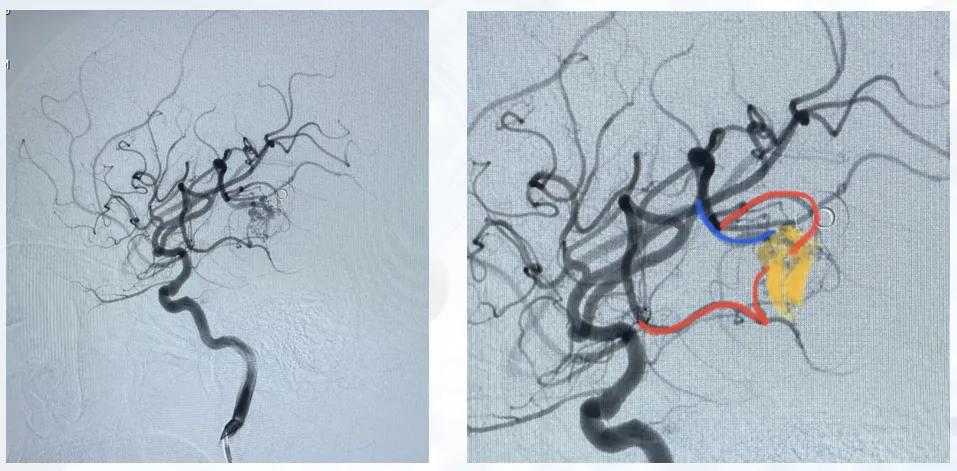

患者因行走偏斜2个月就诊,MRI检查提示颅内畸形,血管造影明确颅内存在5处动静脉畸形,累及双侧脑组织,同时合并硬脑膜动静脉瘘,右侧畸形可见静脉湖、深静脉引流及脉络膜前动脉动脉瘤。初始未发生破裂,因病变复杂未予手术处理,建议定期影像学复查。出院1个多月后患者突发意识障碍,头颅检查提示右侧颞顶叶大量出血。回顾术前影像,右侧畸形结构更为复杂,存在动脉瘤、深静脉引流等多个高危因素,与破裂危险因素的预测相吻合。

图7 右侧颈内血管造影

图8 左侧颈内血管造影

图9 左:左侧颈外血管造影;右:椎动脉血管造影